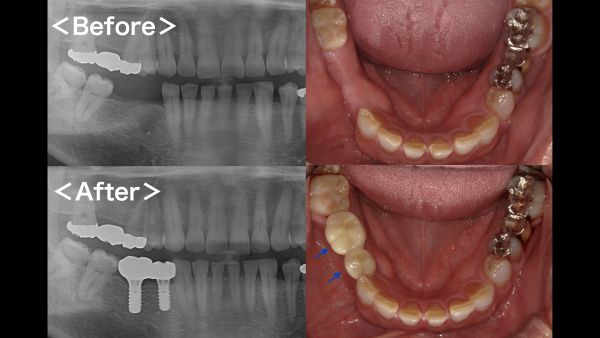

こちらがその時のレントゲン写真になります。

右下4番目と7番目の歯でブリッジが入っておりました。右下4番目の歯の周囲に薄く骨が溶けている像が見られました。

数ヶ月後のメインテナンス時にレントゲン写真を撮影したところ、周囲の歯の骨の吸収が進んでいることが分かりました。

処置時間は40分程度で問題なく終了しました。処置後のレントゲン写真がこちらになります。

被せ物(ジルコニア)が出来上がってきましたので、微調整を行い、お口の中にセットしました。セット後のお口の中の写真とレントゲン写真がこちらになります。